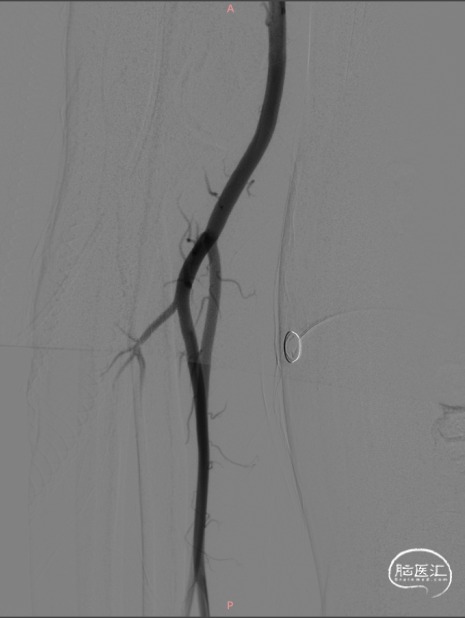

CCJ AVF完全不显影

治疗结果

右侧椎动脉造影CCJ AVF完全不显影,左侧PICA保护良好

左侧椎动脉造影不见CCJ AVF显影

右椎造影,未见CCJ AVF复发

左椎无供血